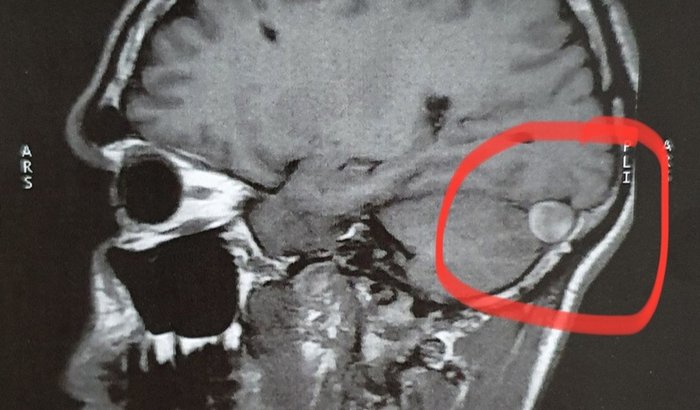

Olá, no ano de 2017 eu retirei um tumor do crânio por cirurgia, quando descobri eu estava com hidrocefalia pois o tumor tinha aproximadamente 7cm, tbm tive meningite bacteriana e tive algumas sequelas, como; dores de cabeça crônicas, tonturas, problemas no sistema nervoso e motores e, tenho que estar fazendo alguns tratamentos, como; fisioterapia, alimentação adequada e etc e venho pedir a ajuda de vcs pois ainda não consegui auxílio do governo e não estou conseguindo arcar com nossas despesas de tratamento. Eu moto com minha mãe que é aposentada e o salário dela não está dando pra arcar tbm, ela sofre com síndrome do pânico e uma depressão muito forte, venho pedir a ajuda de vcs para estar conseguindo pagar meus tratamentos e poder ajudar minha mãe em casa pois ela é muito dependente de mim e eu tenho que estar bem para ajudá-la, se vc sentir no seu coração que pode estar contribuindo eu fico muito feliz e que Deus abençoe sua vida e se não puder com dinheiro pode ser com oração tbm!! 🙏🏽🙌🏽❤️